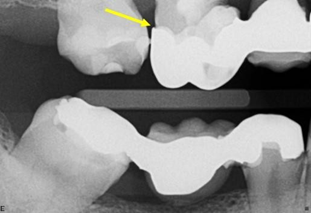

Figure 3Interproximal radiography of the molars and premolars D region, diagnosed on panoramic radiography. The arrows point to the distal of tooth 45, showing excess of amalgam restoration, in the distal box, which characterize iatrogeny. Note that the alveolar bone crest is already in the process of resorption.

Figure 6 Panoramic radiographic technique performed with the Frankfurt Plan slightly higher than the standard position, to "open" the interproximal spaces in the posterior teeth, making the smile line straighter .